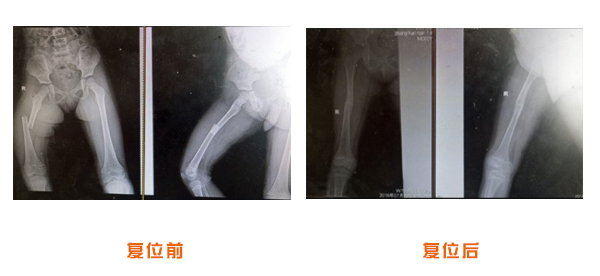

復(fù)位前后對比